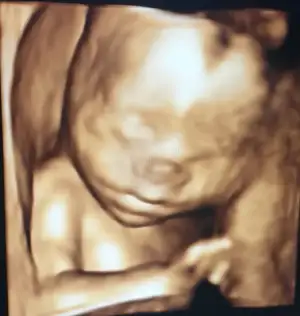

Yarım saat sürdü. Sata göre 20+6 yım ultrasonda 21+5 çıktı. 424 gram, 24.5 cm boyunca bir kızçem var

Eli hep yüzündeydi fotolarda ama bir kaç tane alabildik. Ekliyorum♥